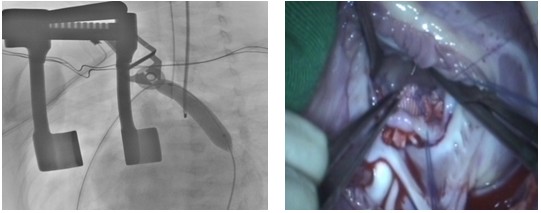

婴幼儿主动脉缩窄合并室间隔缺损比较常见,该类患儿较早出现严重肺充血和重度肺动脉高压, 往往表现为喂养困难, 低体重, 反复呼吸道感染和心衰,因而需尽早手术。目前大多医生采用正中切口,一次性外科手术解除主动脉缩窄和并修补室缺,但需要深低温停循环和局部脑灌注,手术时间长, 创伤大,术后恢复亦颇费周折。为提高此类患儿的疗效,阜外医院自2008年起采用Hybrid 技术一期经胸矫治小婴儿主动脉缩窄合并室间隔缺损,首次将球囊扩张术融入心脏外科手术中。与经皮球囊成形术相比,其操作明显简单, 有效避免了经外周血管径路受限及股动脉损伤等问题。与常规外科手术相比,可简化手术,免除深低温停循环或局部脑灌注, 明显缩短手术时间, 促进术后恢复。该项技术对于病情危重, 反复肺部感染, 严重营养不良的主动脉缩窄合并室间隔缺损的小婴儿, 不失为一种简单、安全、有效的可选择的方法。

图注:在一站式杂交手术室内同期进行主动脉狭窄球囊扩张术(左)及室间隔缺损修补术(右)